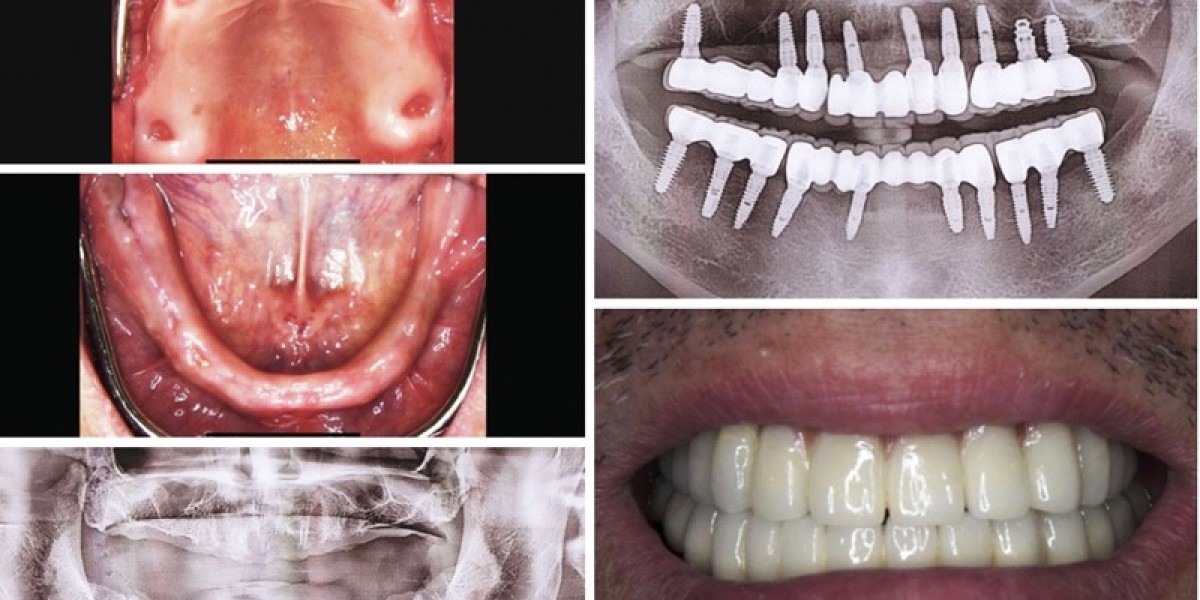

Norcross Dental Care You Can Trust: Complete Family Dentistry at Berkeley Lake Dental | #norcross dental

Norcross Dental Care You Can Trust: Complete Family Dentistry at Berkeley Lake Dental

We believe that exceptional Norcross dental care goes beyond treating teeth—it’s about building relationships and improving overall well-being.